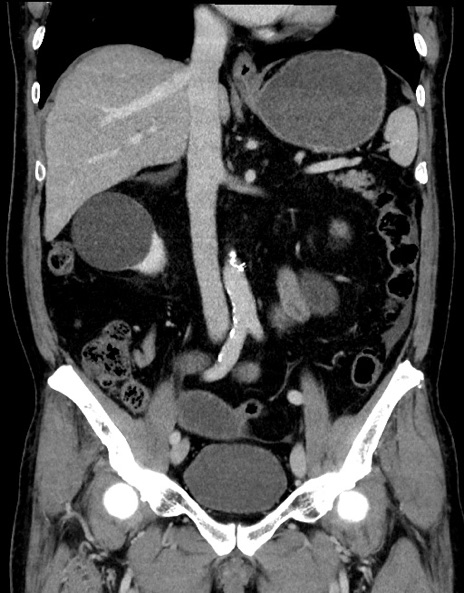

症例15(冠状断像)

【症例】70歳代男性

【主訴】腹痛

【現病歴】今朝から腹痛あり。全体的に痛い。特に左上の方。排ガスが今日はない。冷や汗が出る。

【既往歴】直腸癌術後

【身体所見】左側腹部〜上腹部に圧痛あり。腹膜刺激症状明らかなではない。軽度反跳痛。左下腹部に術後瘢痕あり。

【データ】WBC 7700、CRP 0.02